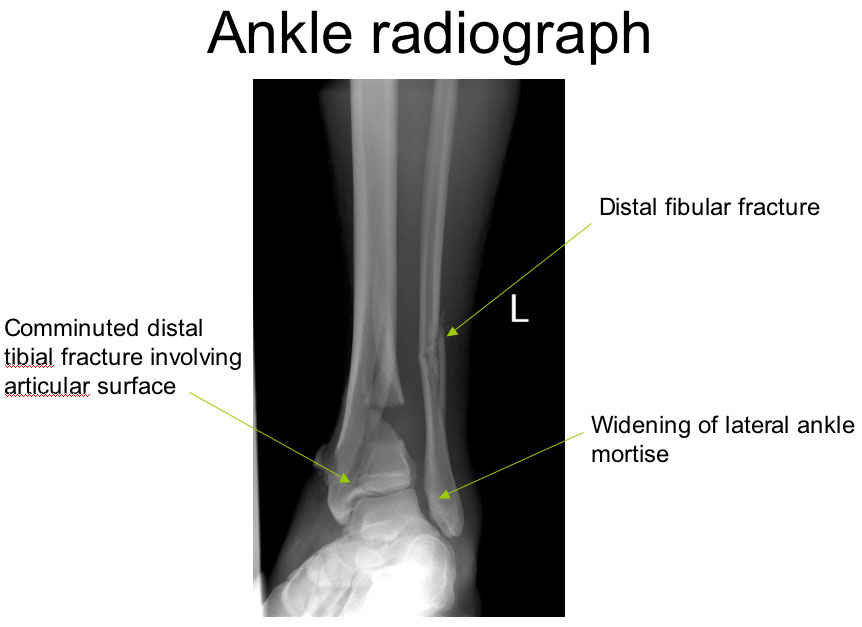

An 18 year old male arrives in the ED by ambulance. The patient stated to the paramedics that he was struck by a car several hours prior to calling 911. He is now complaining of worsening left leg and ankle pain and is also having increased difficulty walking. Upon arrival in the ED, his left leg appears deformed proximal to the ankle. Additionally, the distal 1/3 of his left leg is now mottled and swollen. ED staff is unable to palpate left dorsalis pedis or posterior tibial pulses. X-rays show fractures of his left tibia and fibula; his leg continues to swell, and his pain continues to increase despite medication. The patient is diagnosed with compartment syndrome of the left lower leg and receives fasciotomies of all four compartments of his left lower leg as well as his foot. The patient's pain diminished after the fasciotomies and a weak dorsalis pedis pulse returned. An arteriogram was performed and showed occlusion of the patient's left fibular (peroneal) artery in the area of the fractures. It also showed perfusion of the dorsal arch of the left foot via collateral circulation. Because circulation was returned to his foot, surgical repair of the left fibular artery was not pursued.